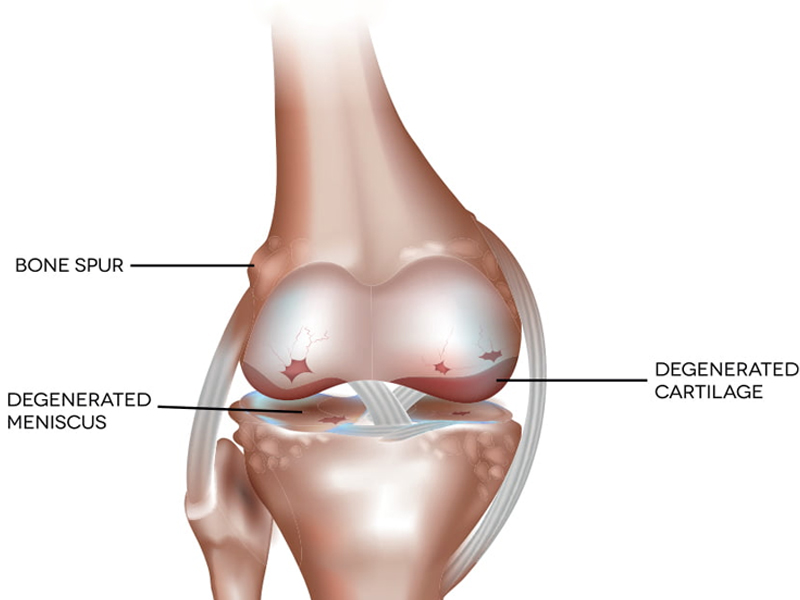

Knee Arthroscopy

Knee arthroscopy is a surgical procedure that allows doctors to view the knee joint without making...

Cartilage preservation procedures

Articular cartilage is the smooth, white tissue that covers the ends of bones where they come together to form ...